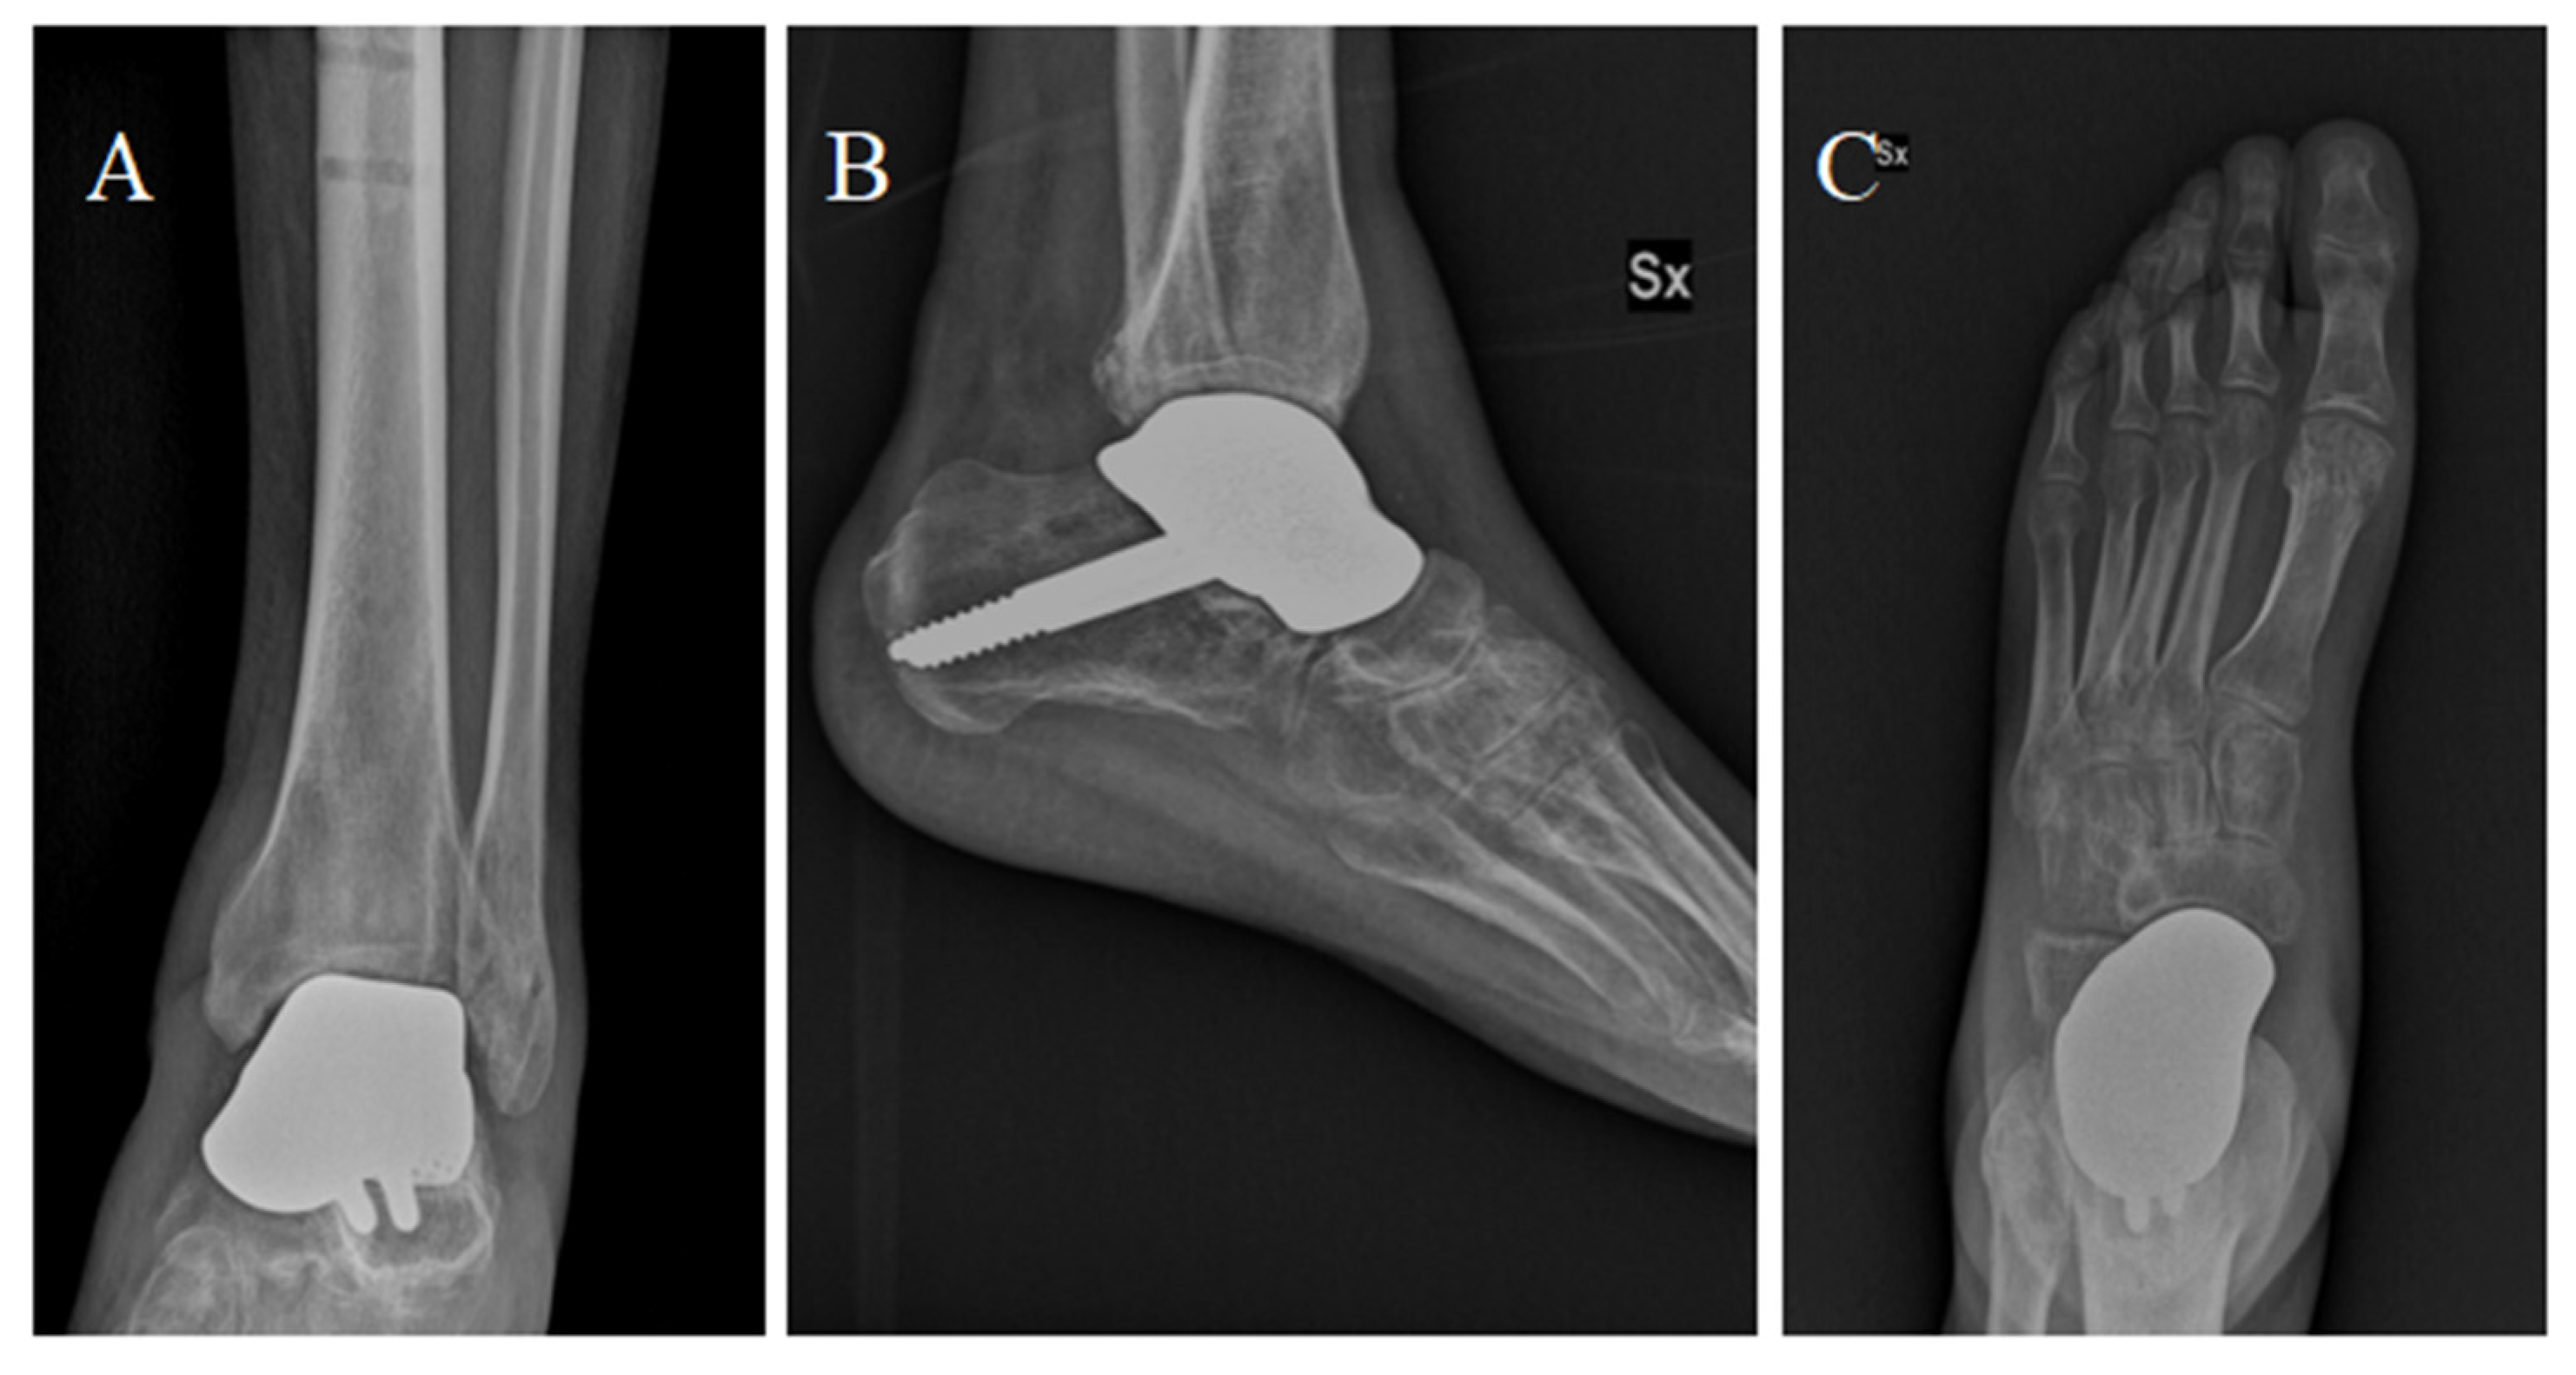

Percutaneous Achilles tendon lengthening was performed to improve ankle dorsiflexion. After surgery, a plaster cast was applied for 3 weeks. After 3 weeks, partial weight bearing was allowed, with full weight bearing within 9 weeks of surgery. We decided to examine the patient at 1, 2, 4, 6, and 12 months after surgery, and then once a year (Figure 5). The patient was satisfied with the outcome of the surgery and showed good functional results: At 6 months, he presented an AOFAS (American Orthopedic Foot and Ankle Society Score) of 86 and an NRS (Numeric Rating Scale) of 2. The sagittal range of motion (ROM) was >30°. The patient satisfaction as well as the clinical scores were retained at the 12-month follow-up.

Figure 5.

Anterior-posterior (A), dorsoplantar (B) and latero-lateral (C) projections showing the implant at the 6-month follow-up after surgery.